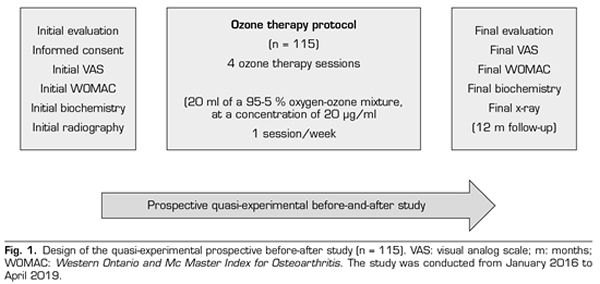

A prospective quasi-experimental before and after study was performed. A total of 115 patients with knee osteoarthritis with Kellgren-Lawrence (KL) grade 2 or more, who attended the Santa Cristina University Hospital, with clinical symptoms (pain, stiffness, loss of function), requiring conservative treatment, and in who previous symptomatic treatment failed were included in the study. The study was conducted from January 2016 to April 2019 and it was authorized by the Ethics Committee of the University Hospital of Santa Cristina, after signing an informed consent (Figure 1).

During the initial assessment, the treatment objectives, the procedure, the indications and contraindications were explained, the initial biochemical evaluation (analysis of CRP, ESR and uric acid) and the initial radiography of the knees were performed, the clinical scales (VAS and WOMAC) were provided and the informed consent was signed (Figure 1). We did not assess joint mobility in this study, because it was not considered as an outcome variable.

Methods: A prospective quasi-experimental before-and-after study was performed in 115 patients with knee osteoarthritis Kellgren-Lawrence grade 2 or more. The ozone protocol consisted of 4 sessions (one session / week) of an intra-articular injection of 20 ml of a medical mixture of Oxygen-Ozone (95-5ºC) at a concentration of 20 µg / ml. Outcome variables included clinical (pain, stiffness, and function), biochemical (CRP, ESR, uric acid), and radiological variables (minimal femorotibial joint space).